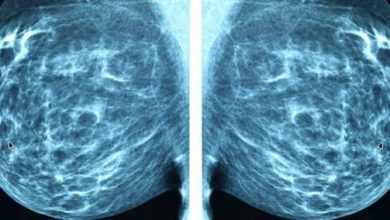

رسميًا: الذكاء الاصطناعي يتفوق على الخبراء البشريين في تشخيص سرطان الثدي

صرح فريق من الخبراء التقنيين أن الذكاء الاصطناعي يتفوق على الخبراء البشريين في الوقت الحالي فيما يتعلق بتشخيص سرطان الثدي.…